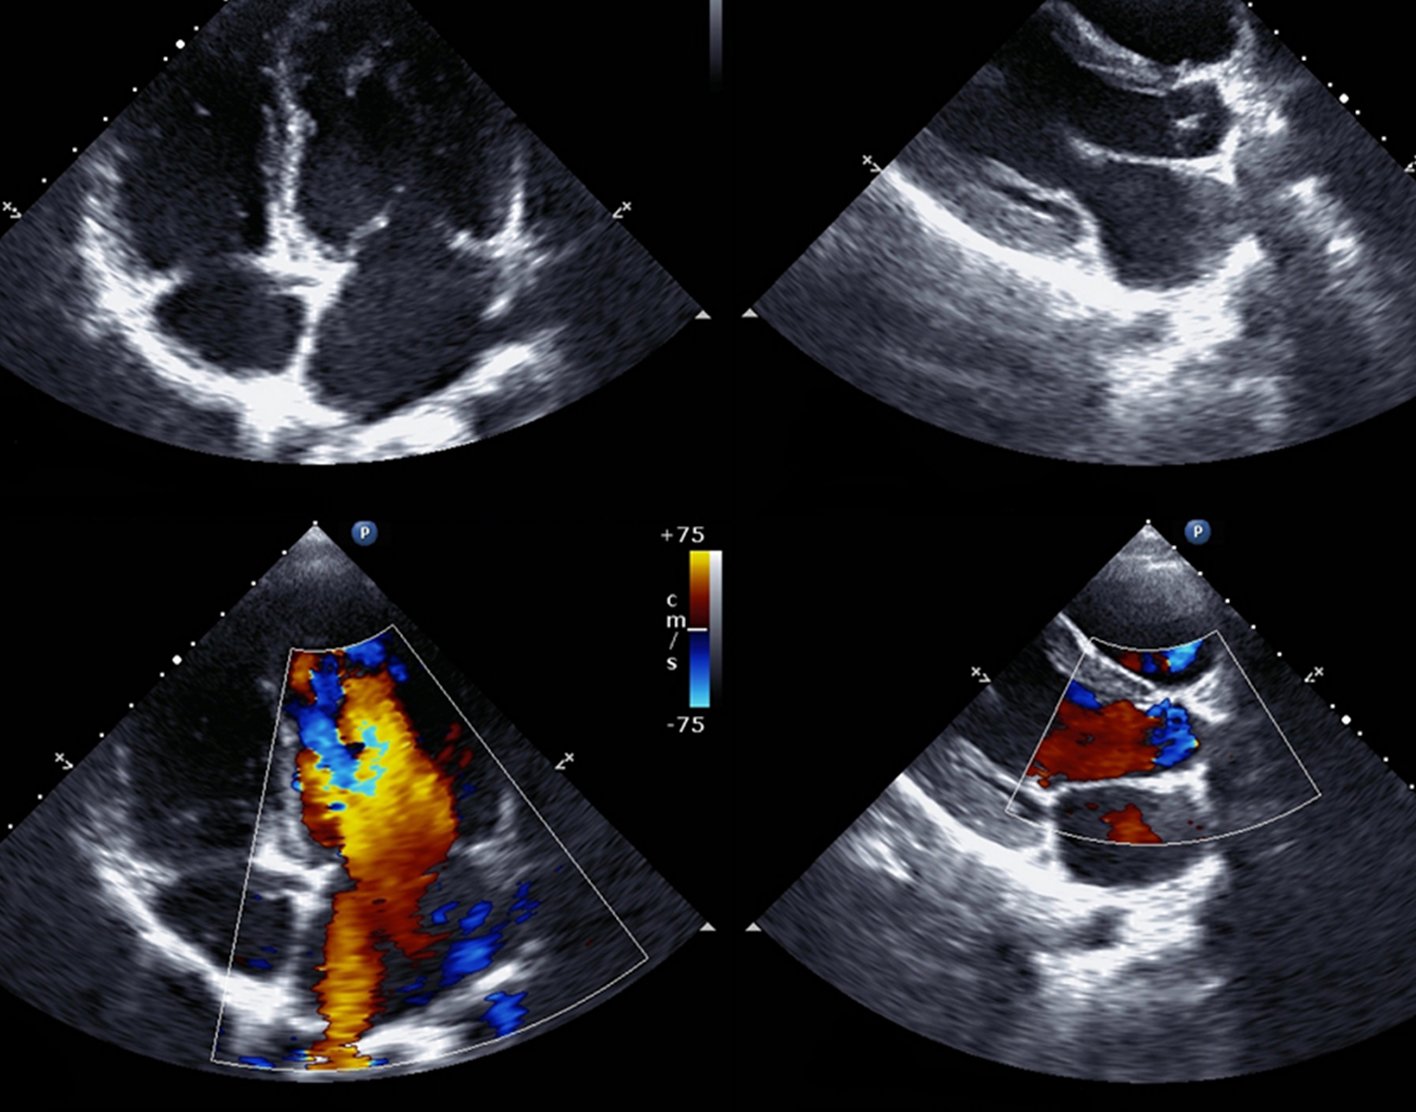

An echocardiogram is a test that uses sound waves to create pictures of the heart. The picture and information it produces is more detailed than a standard

- Images can be two-dimensional or three-dimensional. The type of image will depend on the part of the heart being evaluated and the type of machine.

- A Doppler echocardiogram evaluates the motion of blood through the heart.

An echocardiogram shows the heart while it is beating. It also shows the heart valves and other structures.